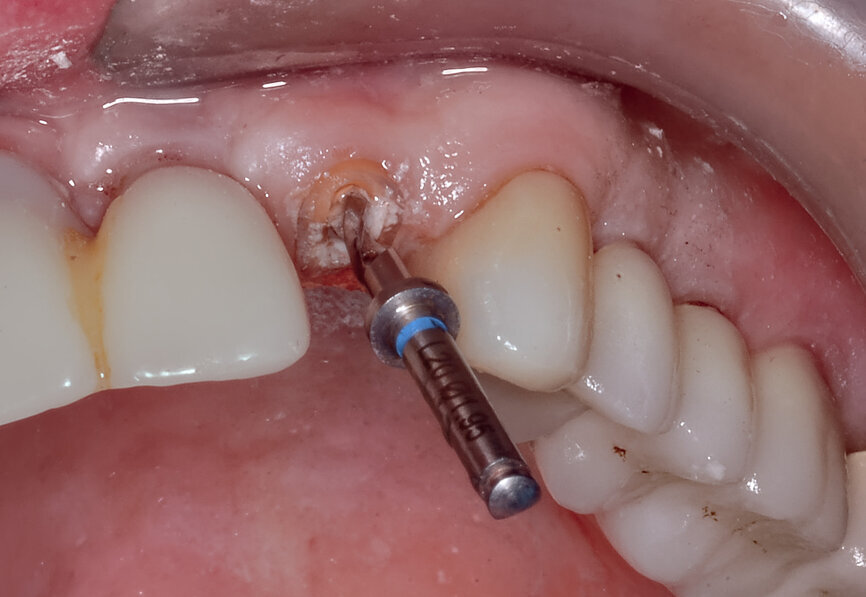

Fig. 12a: A post fracture presenting in the left central incisor, requiring extraction.

Fig. 12b: The occlusal view illustrated the cervical tissue volume and contours.

A 62-year-old male patient presented with a hopeless prognosis for a post fracture in the left central incisor requiring extraction (Figs. 12a & b). The preoperative periapical radiograph revealed an existing implant supporting a metal–ceramic restoration for the adjacent region #11 (Fig. 13). The CBCT (CS 9600, Carestream Dental) cross-sectional image revealed a favourable preoperative condition relating to the trajectory of the endodontically treated root to the alveolus for a PET procedure (Fig. 14a). Using the native Carestream 3D Imaging software, a simulated implant and abutment projection was positioned within the available bone to avoid the root fragment (Fig. 14b).